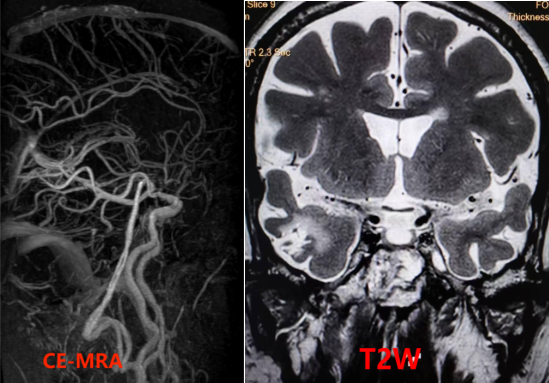

4招丨发现血管炎性病变

c942acd936317f3ed8349105fac4e327.png

左图T1W平扫见大脑中动脉M2段管壁增厚明显并呈等高信号,右图T1W增强后见管壁强化明显,提示该处有活动性炎症。

91afb25b92d13a6bf5254e21724c0d78.png

3D曲面重建后更直观明确血管壁炎症的位置和情况。